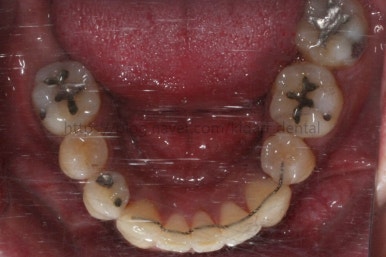

치료 시작 3개월째의 모습입니다.

서서히 가지런해지는 느낌이 드시나요?

화살표를 보면 작은 어금니 하나가 아래로 꺼져있는데, 이 녀석 때문에 애를 먹었네요. 훨씬 치료가 빨리 끝날 수 있었는데 이 치아가 워낙 잘 안움직이는 바람에 2년 개월정도로 치료기간이 많이 걸린 편이었어요.

치료 8개월째의 모습입니다.

이제 얼핏 보면 매우 가지런해졌어요. 이 뽑은 자리도 많이 남지 않았고 왼쪽 위 송곳니가 없지만 그리 표시도 많이 나지 않네요.

대신 위쪽 아래 작은 어금니가 애를 먹이고 있어요. 낚시줄처럼 부여매고 끌어올리는게 보이실거에요.

뼈에 단단히 붙어 안움직이는 경우를 "유착치아"라고 표현하는데, 유착치아라면 해당 치아를 움직이는 것을 포기했어야 했어요.

그래도 조금씩이라도 움직이고 있어서 계속 시도했습니다.